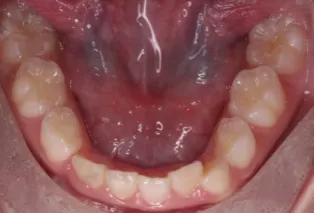

Intraoral photos